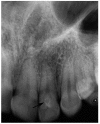

Results: Dens invaginatus was observed in 116 of 4556 subjects, with a frequency of 2.5%. There was only one periapical lesion in teeth with type I dens invaginatus, but 8.1% of patients with type II and 87.5% of patients with type III dens invaginatus had apical periodontitis at the time of referral. There were 116 (72%) females and 32 (27%) males with dens invaginatus.

Conclusion: This data represents the only study carried out in a large population in Turkey, and no dens invaginatus was found in mandibular teeth. The most commonly observed type of dens invaginatus was type I (69.8%).